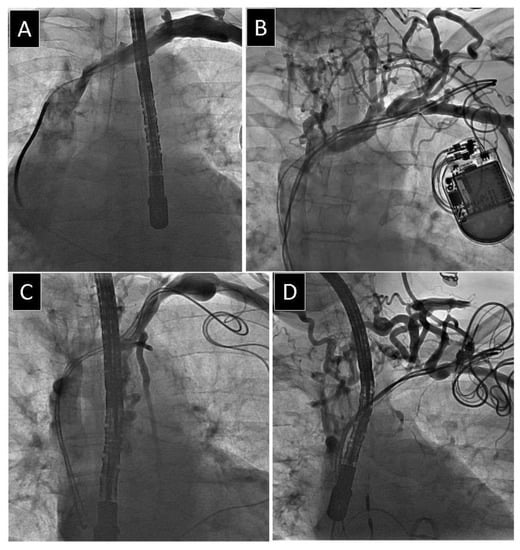

2.2. Venography

2.3. Lead Extraction Procedure